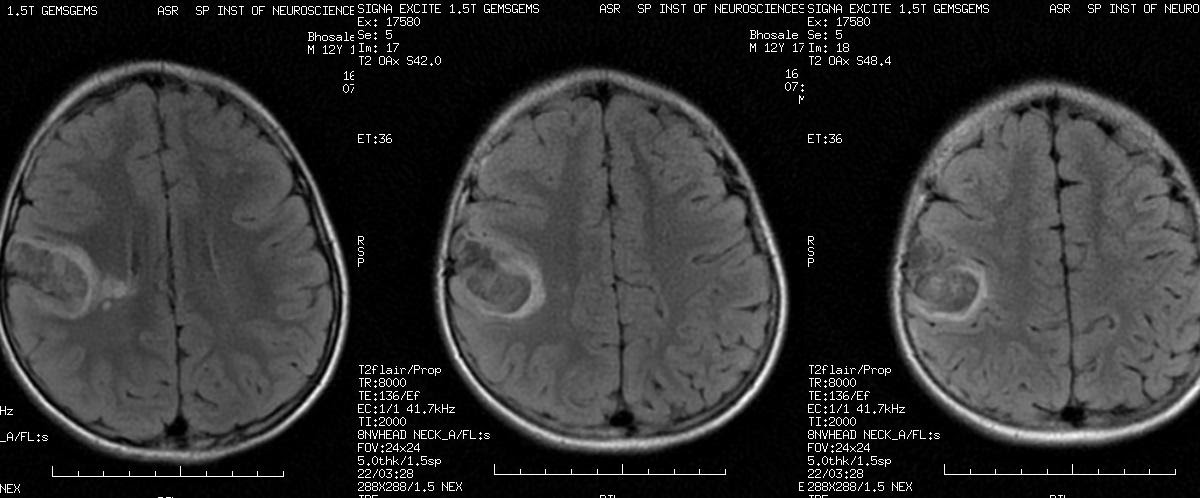

La imagen por resonancia magnética (MRI, MRI) o tomografía computarizada (TC) muestra lesiones en la corteza cerebral. Las lesiones se extienden en todo el espesor de la corteza. En la TC se puede ver densas lesiones de la corteza con discapacidad (hipodensa) bien delimitadas . Los quistes se encuentran a menudo calcificados. Una acumulación de medio de contraste no es típica. Un desplazamiento del tejido circundante no se produce. A veces hay una deformidad del cráneo sobre el tumor. En la RM, las lesiones aparecen bien definidas, no invasoras, y sin edema perifocal (captación de líquido en el parénquima cerebral circundante). Como es típico, la configuración multinodular (que consta de muchos como estructuras nodulares) se ha descrito.[1][7]